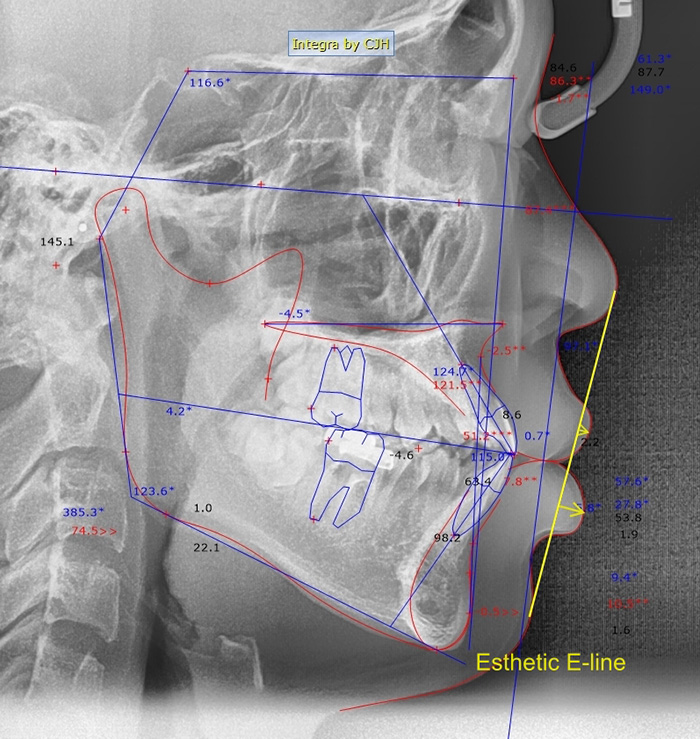

두 번째 기준으로는 안모에 돌출이 있는지도 평가를 해야 합니다. 돌출을 평가하는 가장 많이 알려져 있는 기준은 esthetic E-line이 있습니다. 옆에서 봤을 때 코끝이랑 턱끝을 연결한 선을 기준으로 입술이 이 라인보다 튀어나와 있으면 일반적으로 입이 많이 나와 있다고 생각하시면 됩니다. 코랑 인중 사이의 각도인 비순각이라고 하는 각도도 돌출 평가를 하는데 사용되기도 합니다. 비발치만으로도 약간의 돌출 정도는 충분히 개선이 가능합니다. 하지만 누가 봐도 티가 나는 확실한 돌출 개선 효과를 보기 위해서는 입을 넣기 위해서 발치 교정이 필요하게 됩니다.

Esthetic E-line